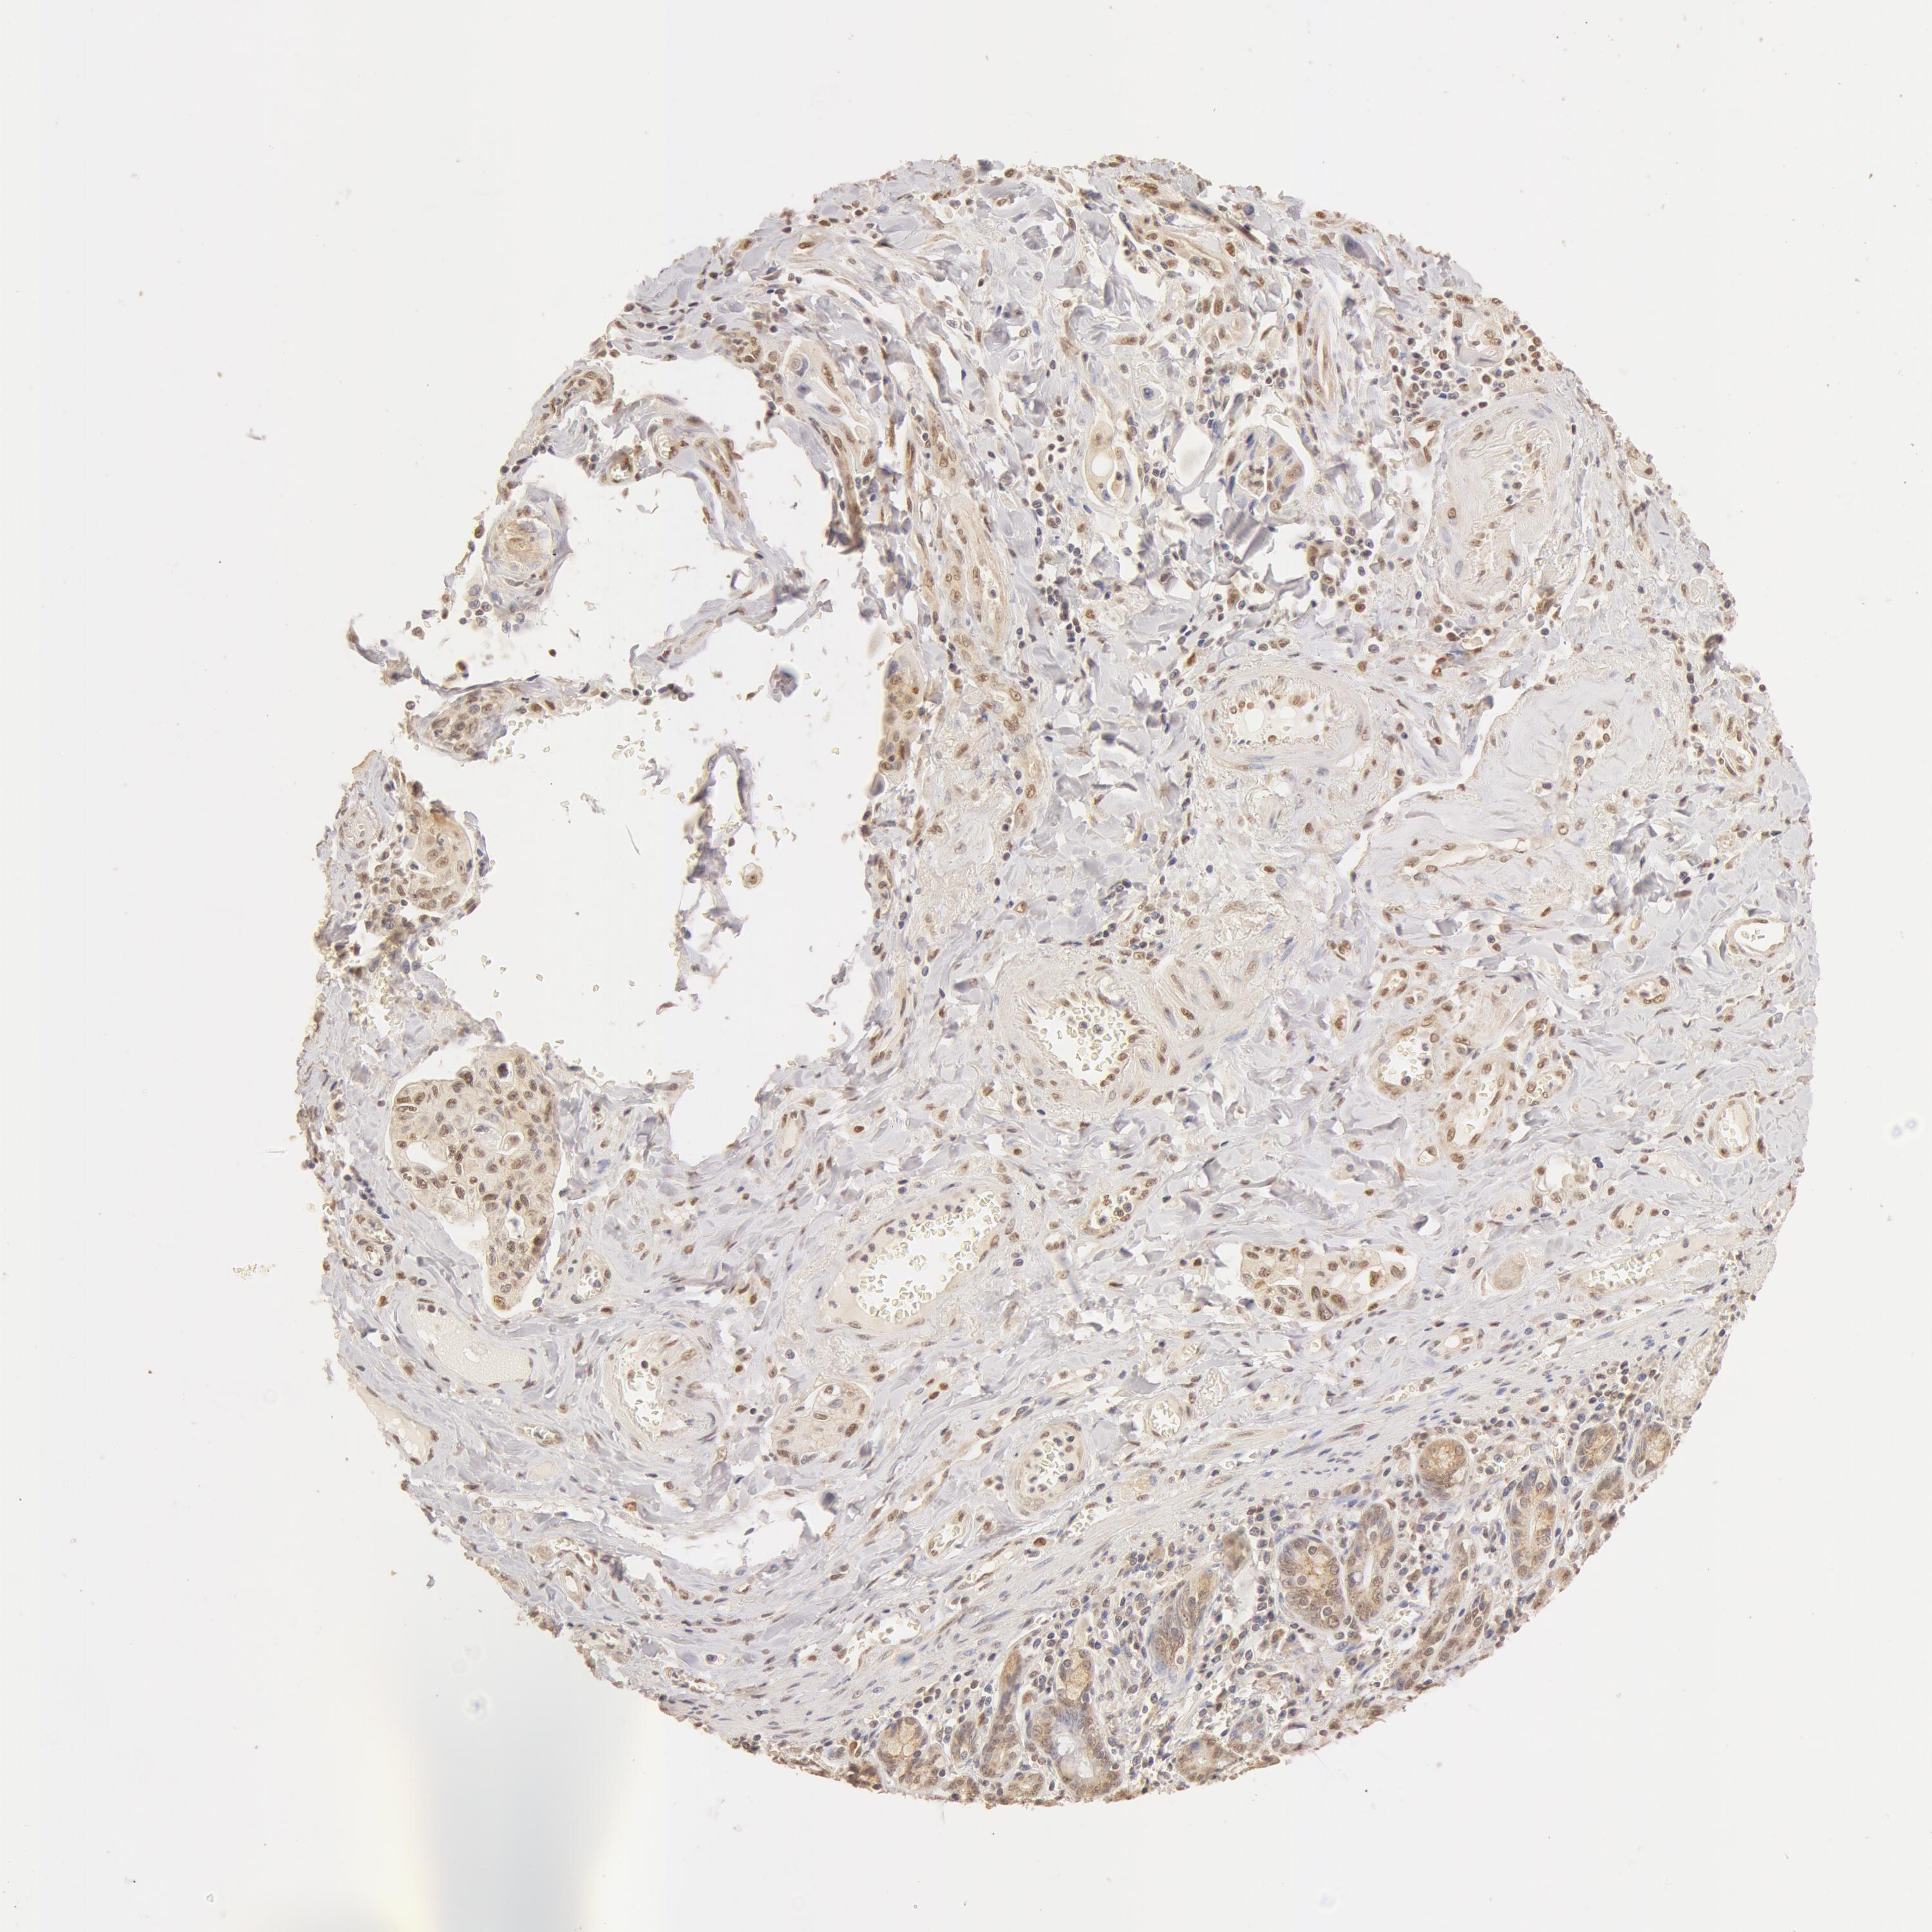

PANCREATIC CANCER - Protein expressioni

A mouse-over function shows sample information and annotation data. Click on an image to view it in a full screen mode. Samples can be filtered based on level of antibody staining by selecting one or several of the following categories: high, medium, low and not detected. The assay and annotation is described here.

Note that samples used for immunohistochemistry by the Human Protein Atlas do not correspond to samples in the TCGA dataset.

Antibody stainingi

Antibody staining in the annotated cell types in the current human tissue is reported as not detected, low, medium, or high, based on conventional immunohistochemistry profiling in selected tissues. This score is based on the combination of the staining intensity and fraction of stained cells.

Each image is clickable and will lead to virtual microscopy that enables deeper exploration of all samples and also displays staining intensity scores, fraction scores and subcellular localization as well as patient and tissue information for each sample.

Antibody HPA042050

Antibody HPA043516

Antibody CAB001718

Staining

High

Medium

Low

Not detected

Intensity

Strong

Moderate

Weak

Negative

Quantity

>75%

75%-25%

<25%

None

Location

Nuclear

Cytoplasmic/membranous

Cytoplasmic/membranous,nuclear

Adenocarcinoma, NOS